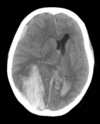

Subdural on CT head

Extradural on CT head

3

5